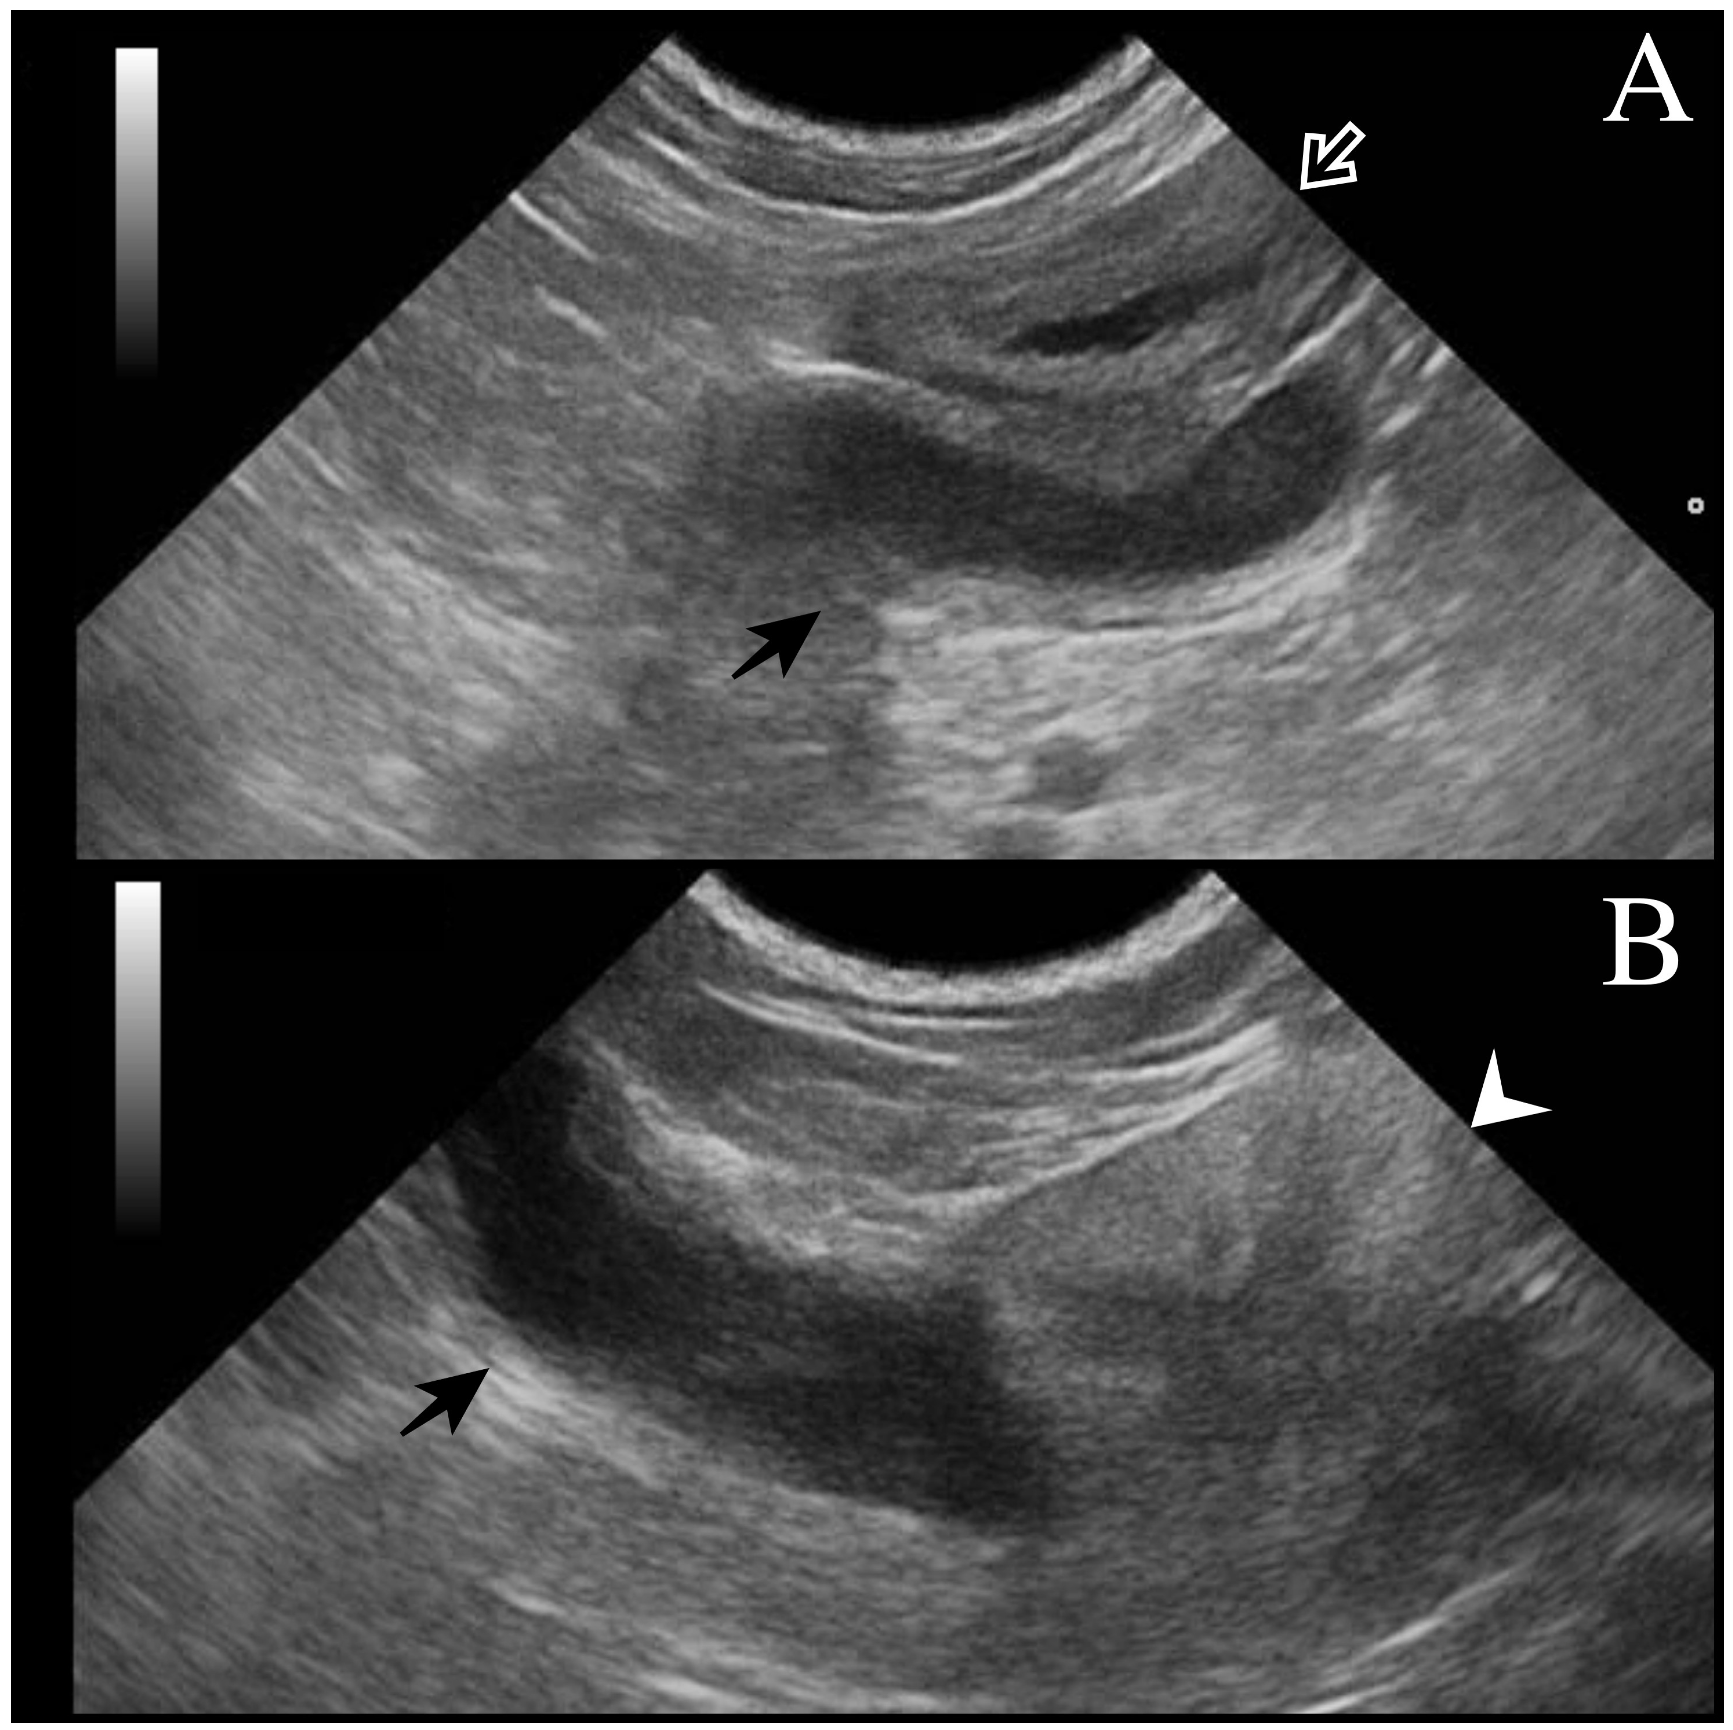

All dogs underwent a complete assessment supplemented with laboratory and ultrasonographic abdominal examination. At presentation, case 1 was asymptomatic, and the tubular fluid-filled structure in the scrotum was detected occasionally by the referring veterinarian during a routine consultation. Cases 2 and 3 presented clinical signs compatible with systemic infection (fever, depression, disorexia/anorexia, vomiting) as described in bitches during pyometra. Except for case 1 (no alterations detected), neutrophilic leukocytosis was observed from the hematological and serum chemistry profiles. In all cases, ultrasound examination revealed a tubular fluid-filled structure with a thin irregular wall located cranially to the prostate and in continuity with the cranial part of the gland (Figure 1). In cases 1 and 2, two other tubular fluid-filled structures were visualized in the caudal part of the abdominal cavity, ventrally to the prostate gland and urinary bladder. In case 3, prostatic metaplasia and preputial keratinization were indicative of hyperestrogenism. Explorative laparotomy was carried out in all dogs, and a bi-horned structure with a stalk connected to the dorso-cranial portion of the prostate gland was recognized. The structure extended caudally in the abdominal cavity engaging in the deep inguinal ring on each side; complete resection was performed in all cases, and in cases 1 and 3, the surgery was completed with orchiectomy. Macroscopically, the bi-horned structure was similar to a fluid-filled female uterus (Figure 2). Table 1 illustrates a comparison of clinical data from the three cases, including anamnestic and clinical details.

Figure 1.

Transverse ultrasonographic image of uterus masculinus: (A) Black arrow points to the uterus masculinus filled with hypoechoic fluid and localized near the urinary bladder (white arrow). The wall of the uterus masculinus is isoechoic to the urinary bladder wall. (B) Uterus masculinus with a fluid-filled lumen (black arrow) originating from the cranial part of the prostate gland (white arrowhead) and extending cranially.